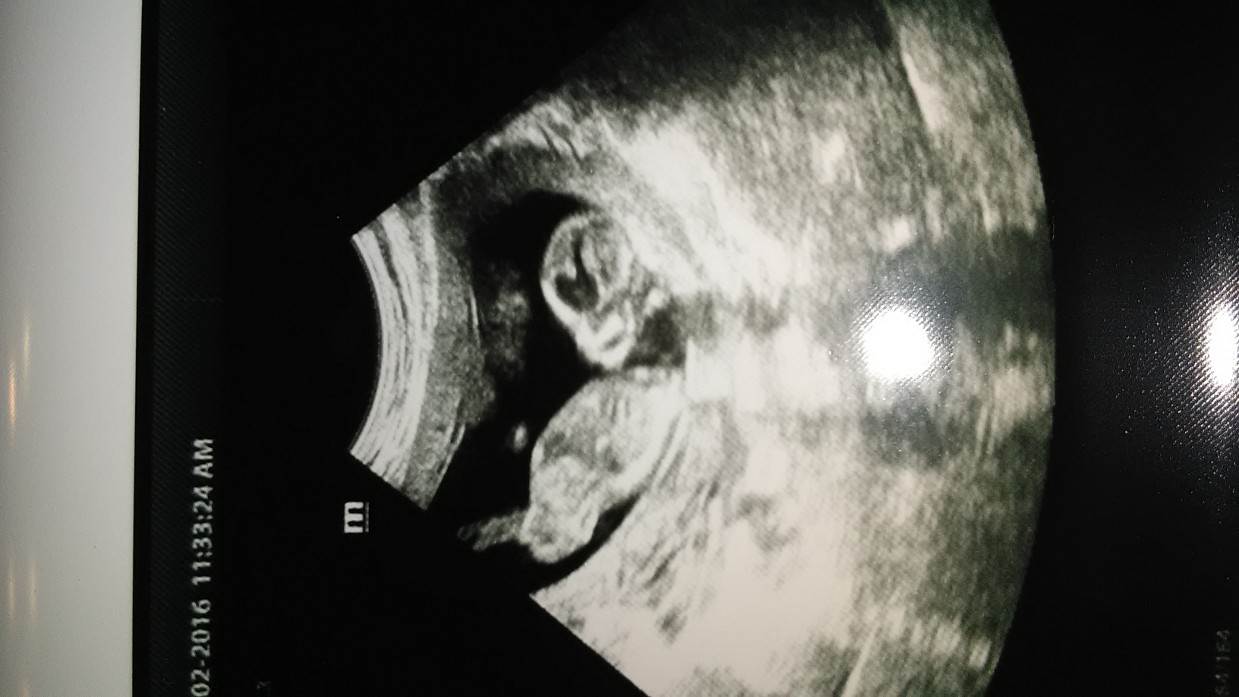

I'm not seeing any bump. Looks very girly to me :)

Girl!